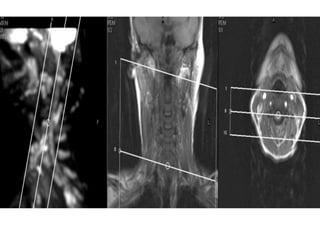

O documento fornece informações sobre como realizar exames de ressonância magnética do pescoço e angiorressonância magnética das carótidas, incluindo parâmetros, programação, anatomia, exames estruturais e funcionais, dicas e protocolos.